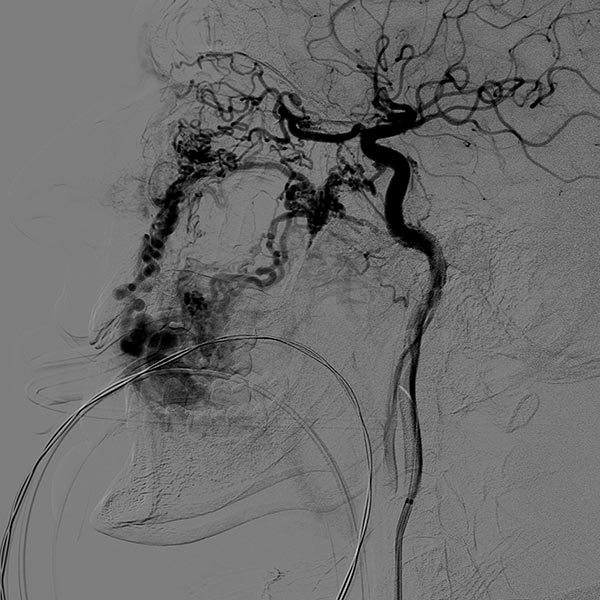

Lateral view, DSA after contrast injection in the left internal carotid artery. There is also a massive supply to the nidus of the AVM from the internal carotid artery, mainly via the ophthalmic artery and the meningohypophyseal trunk.

This complicates embolization therapy considerably.